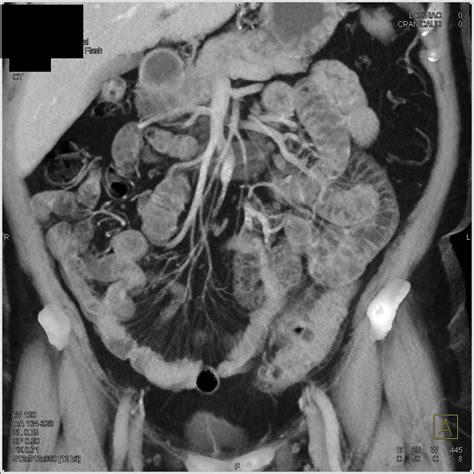

Diverticulitis Sigmoid Colon

• Imaging Tests: Imaging tests such as a CT scan or MRI can provide detailed images of the colon and help confirm the diagnosis.